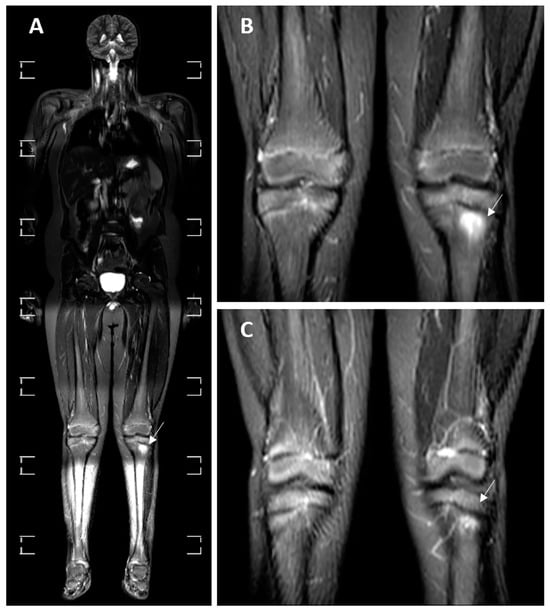

3.4. MRI Findings

| Myositis | 10 (30.30%) | 1 (11.11%) | 6 (85.71%) | 1 (14.29%) | 2 (20%) | p = 0.004 * |